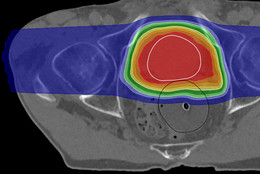

Die Fakultät Physik konzentriert ihre Forschungstätigkeiten in vier Schwerpunkten: Kondensierte Materie, Teilchenphysik, Medizinphysik und Beschleunigerphysik. Die Arbeitsgruppen befassen sich mit aktuellen Themen ihrer entsprechenden Forschungsrichtung und arbeiten an experimentellen oder theoretischen Fragestellungen. Sie sind eingebunden in koordinierte Programme, wie etwa Sonderforschungsbereiche oder Graduiertenkollegs. Die einzelnen Forschungsschwerpunkte sind mit einer Vielzahl außeruniversitärer und auch internationaler Forschungseinrichtungen inhaltlich und personell eng verbunden.